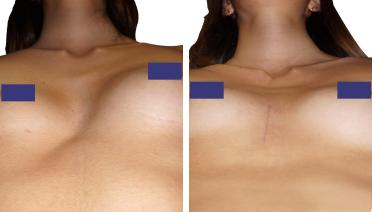

Petto Escavato: risultati prima e dopo

La tecnica di impianto su misura è una tecnica chirurgica minore che consiste nel riempire la concavità creata dal Pectus con un impianto personalizzato. Si tratta di un intervento rapido, a basso rischio, con un risultato immediato e una breve convalescenza.

In questa pagina, troverà i risultati di questa operazione a seconda del tipo di Pectus : mediale, asimmetrico, più o meno profondo o lungo.

Tipo 1 : Mediano, profondo e simmetrico,